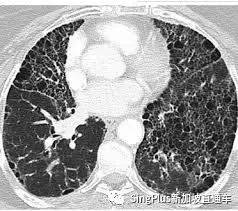

COVID-19被稱爲新冠肺炎,新冠病毒首先引起的就是對肺部的損害。

3月中旬,香港瑪嘉烈醫院傳染中心對首批10名出院病人進行了跟蹤,其中3名治愈者步行加速時會氣促,不能像平常一樣運動,甚至不能像以往一樣工作。

同一時間,首例新冠肺炎屍檢報告發布。

逝者遺體解剖教授劉良表示:

正常的肺含氣,握上去感覺像海綿,但感染新冠病毒的肺一摸就感覺它已經變了,肺裏面被別的東西取代了。

7月18日,法國國家醫學科學院發表了一份有關新冠後遺症的分析報告和建議。法國醫科院成員Patrick Berche教授表示,就算是輕症患者,也會有肺纖維化的後遺症。

肺纖維化會導致呼吸功能衰退,增加呼吸道感染的風險,這簡直就是個定時炸彈。肺纖維化的患者很容易呼吸衰竭而死,這種死因,本質上和淹死是一個道理。

而目前對于肺纖維化沒有特效藥,病情是不可逆轉的。 北京大學第一醫院感染疾病科主任王貴強曾指出:

肺部嚴重感染會發展爲肺纖維化,一部分重症患者治愈後會出現肺纖維,影響日常生活,發展到晚期只能肺移植。